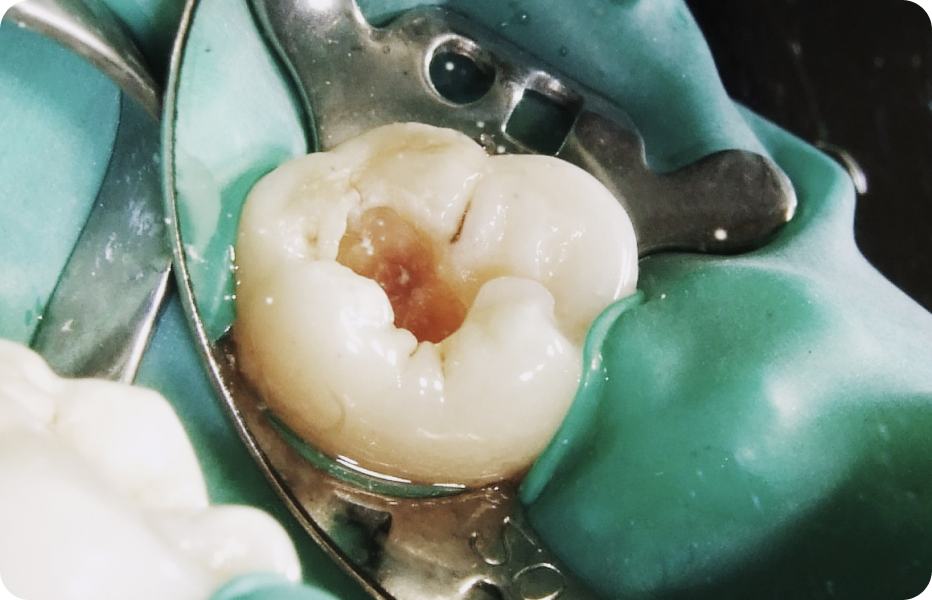

이로운치과는 근관치료, 충치치료 시 러버댐을 사용한 치아 격리 원칙을 최대한 지킵니다.

복합레진을 이용한 수복치료 시 치아 본연의 외형을 재현하려 노력합니다.